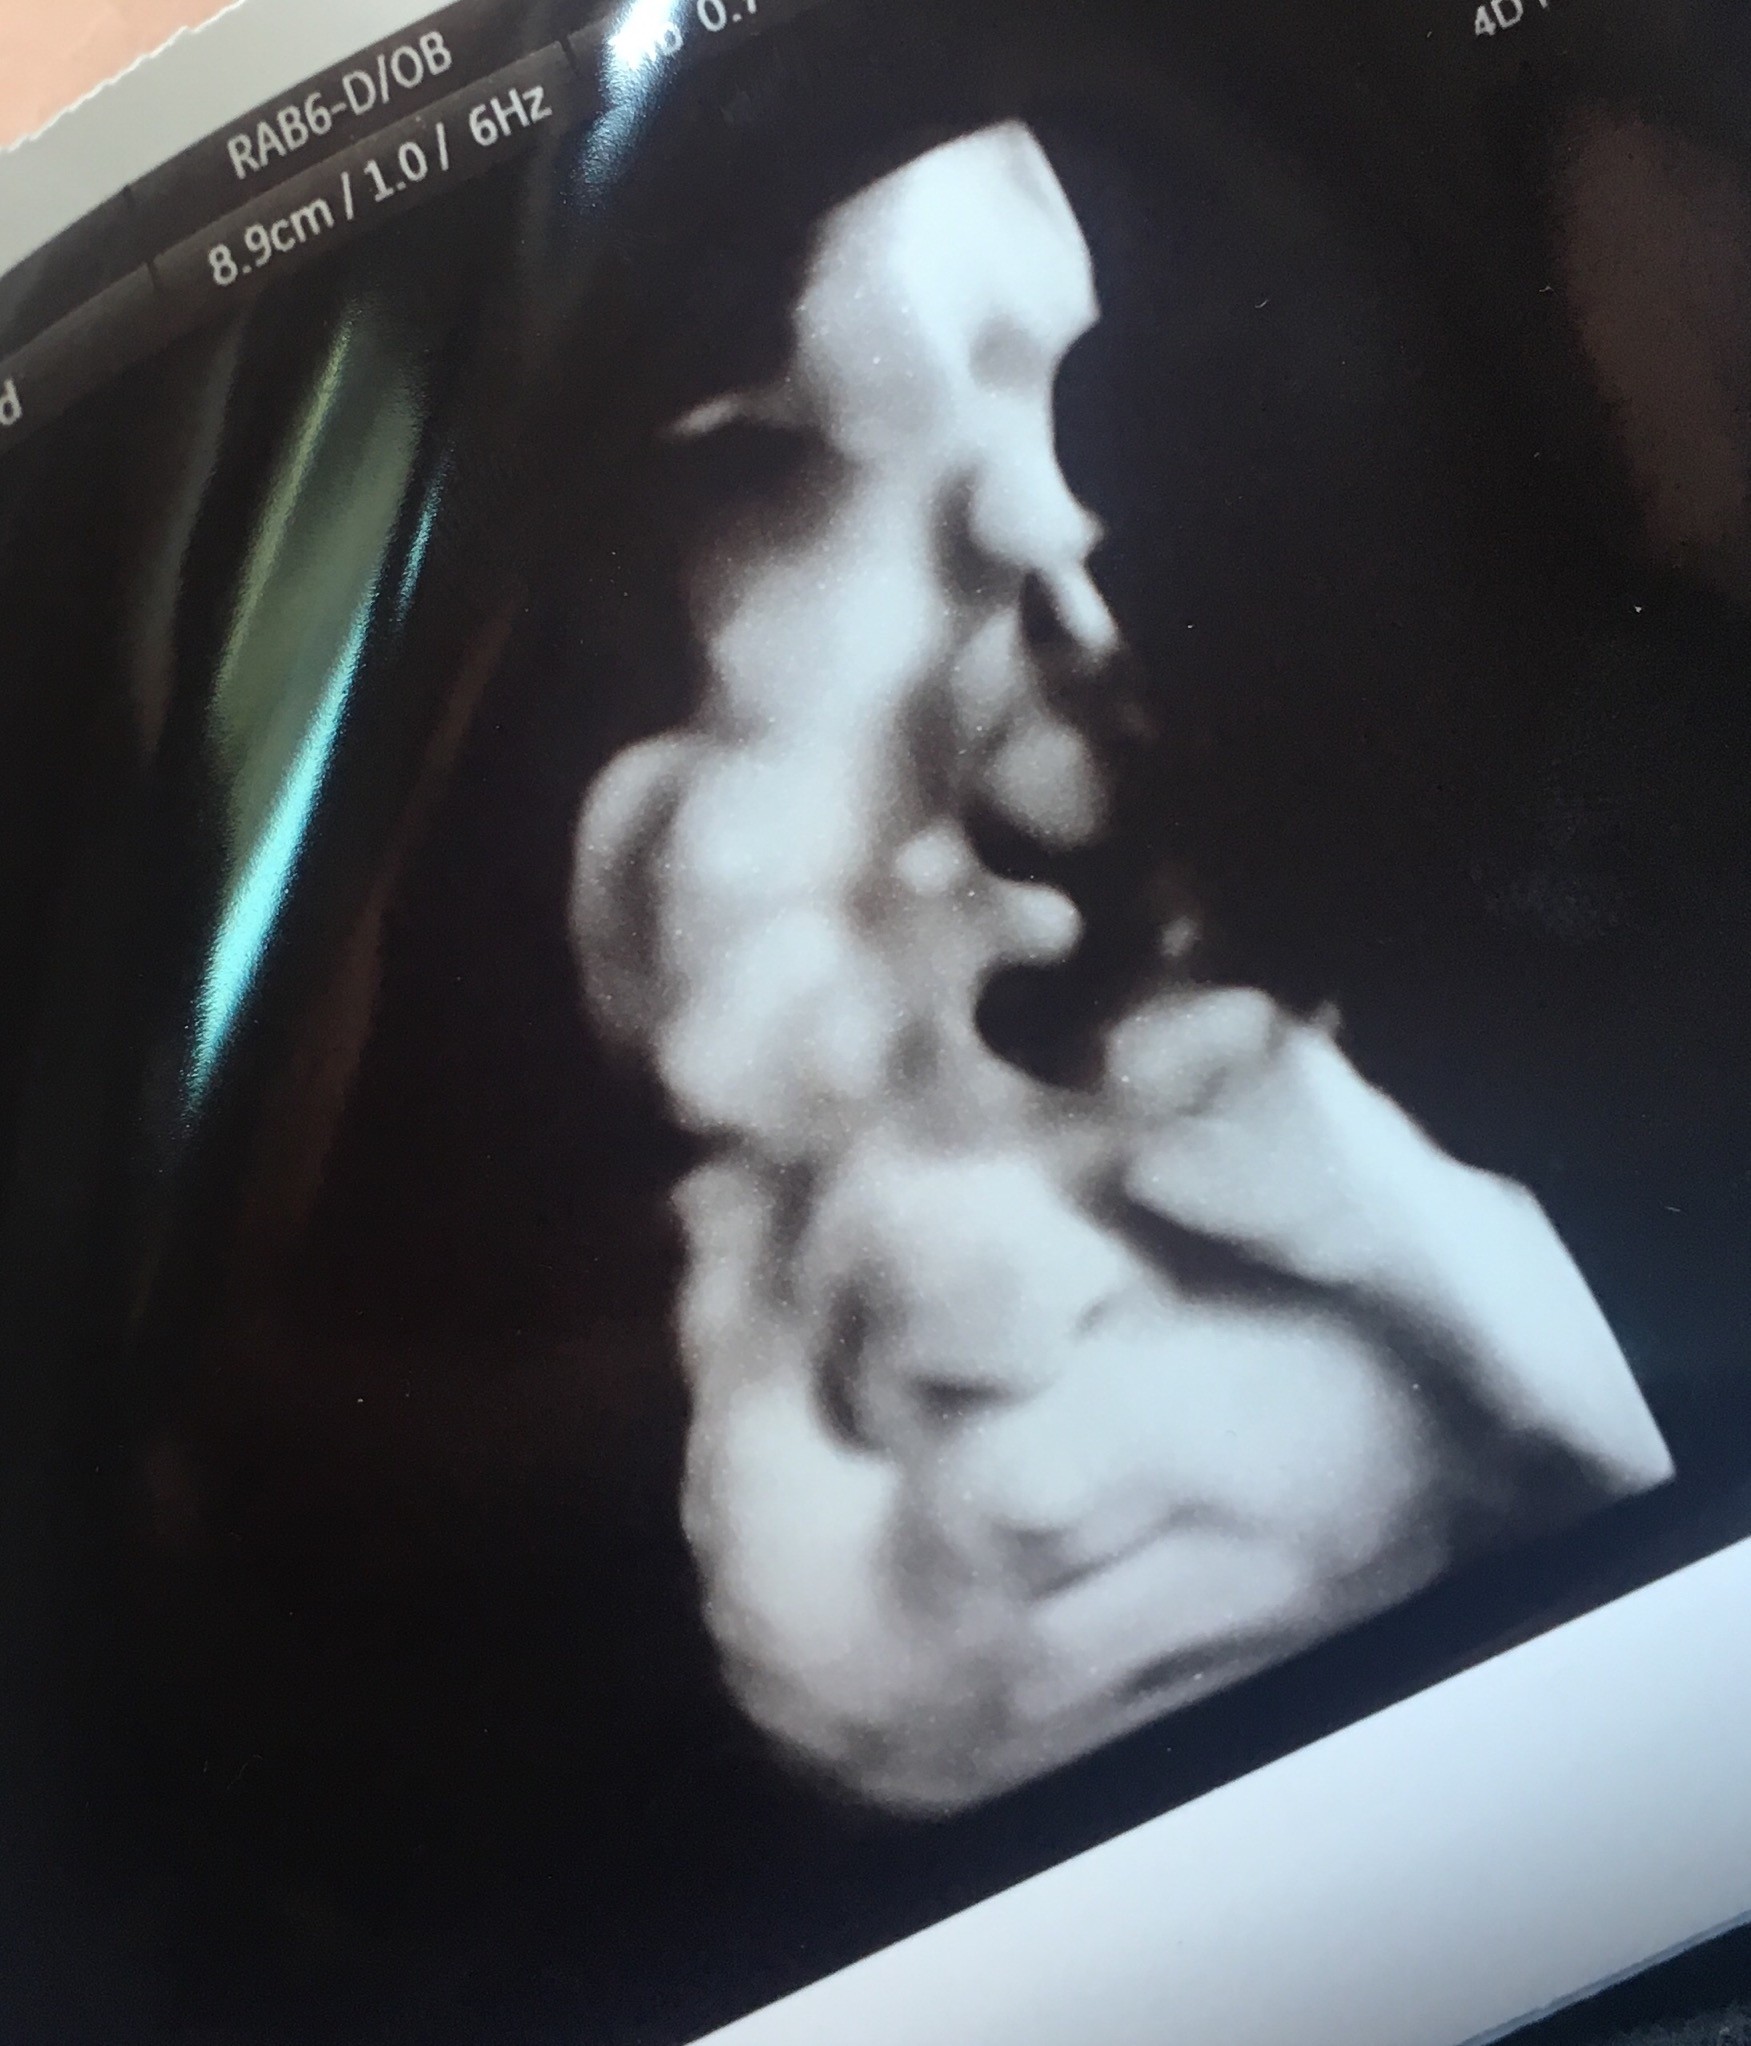

Super wieści. Nasze dziewczyny idą identycznie z wagąWszystko ksiazkowo, aczkolwiek powiedział ze twardnienie brzucha wskazuje na to ze tak jakbym tydz dotrzymała było by idealnie, 18akurat mam urodzinymała wazy 3kg, na 20mam mieć ktg jakby się nic nie wydarzyło do tego czasu... tylko ja mam ciśnienie 145/90 mam sobie je kontrolować codziennie, żebym jakiejś rzucawki nie dostała podczas porodu, mam ostatnie mało wyraźne zdjęcie ale usta jak nic moje

oczywiście rączka od ( miesięcy na główce musi być, nóżki gin powiedział ze już by się nie zmieściły

Zobacz załącznik 886771